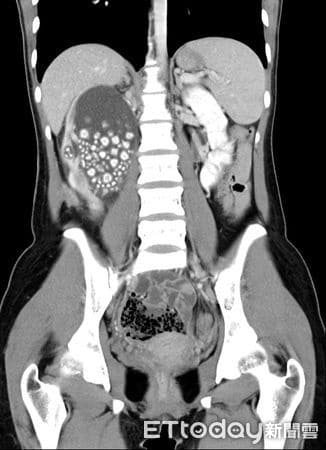

Η νεαρή γυναίκα άρχισε να νιώθει έντονη κόπωση, πυρετό και πόνους στη μέση. Οι γιατροί αρχικά υποψιάστηκαν λοίμωξη του ουροποιητικού ή φλεγμονή των νεφρών — καταστάσεις που αντιμετωπίζονται εύκολα. Όμως οι αξονικές και υπερηχογραφικές εξετάσεις αποκάλυψαν κάτι απίστευτο: το δεξί της νεφρό ήταν διογκωμένο και φραγμένο με εκατοντάδες πέτρες σαν μεγάλους κόκκους άμμου σχεδόν δύο εκατοστών.

Οι περισσότεροι ασθενείς έχουν έναν ή δύο πέτρες. Η νεαρή αυτή γυναίκα είχε εκατοντάδες, που συσσωρεύονταν επί χρόνια λόγω αφυδάτωσης, μέχρι που το σώμα της κατέρρευσε. Οι πέτρες είχαν μπλοκάρει το σύστημα διήθησης των νεφρών, προκαλώντας λοίμωξη και πυρετό.

Oι πέτρες που αφαιρέθηκαν από τα νεφρά της νεαρής κοπέλας

H ακτινογραφία με τις πέτρες πάνω αριστερά